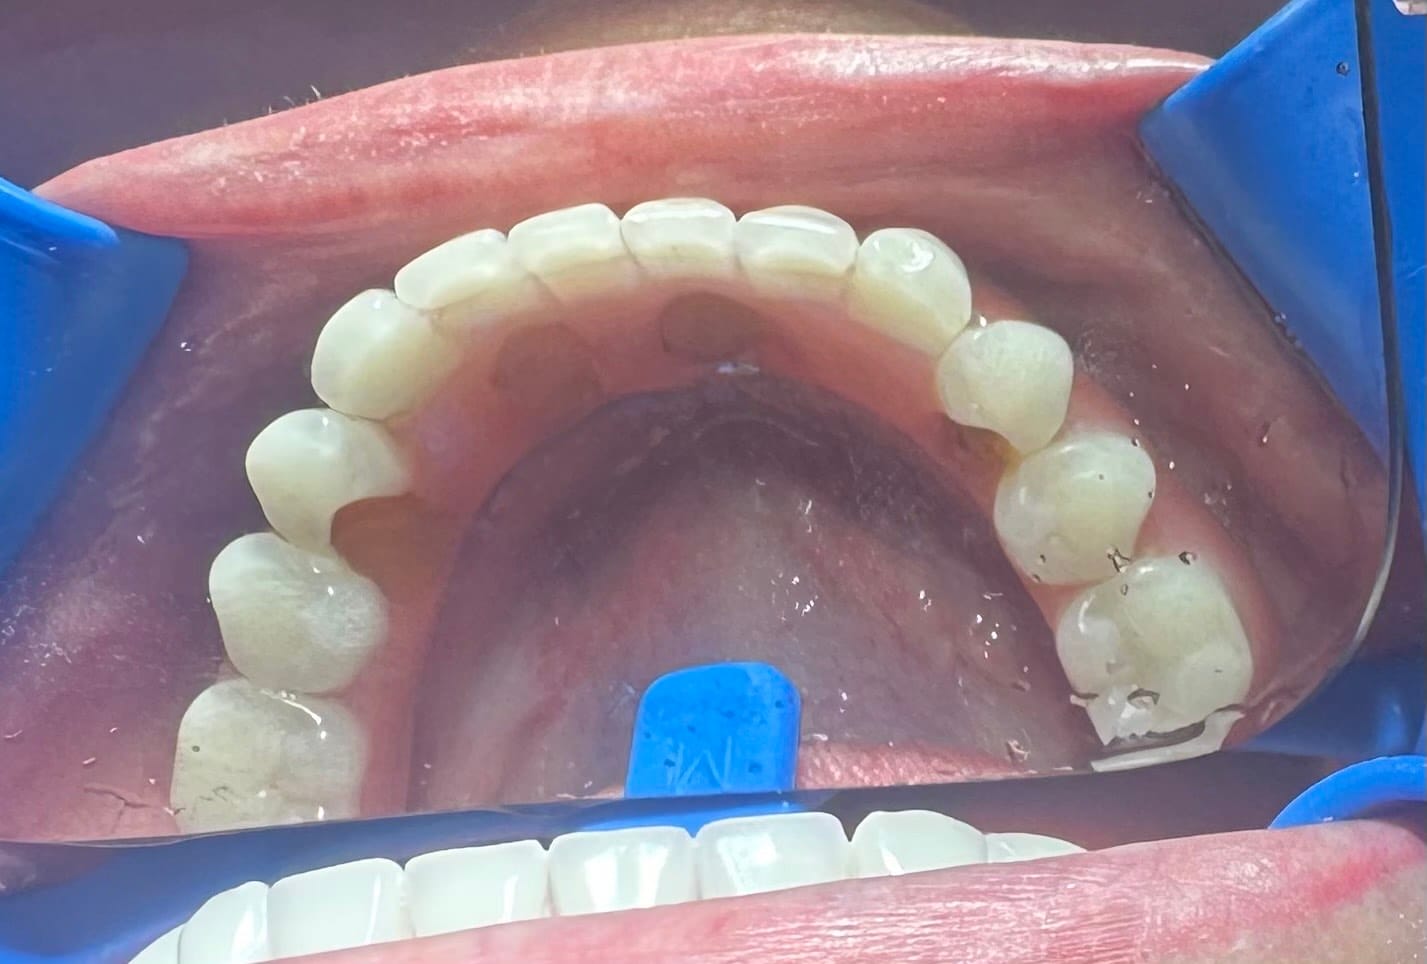

Kaptam néhány fotót, köztük egyet a legutóbbi sérülésről és egy panoráma felvételt.

1. pontosabb mérést kell végezni a fopótlás rágófelszínén…de biztos, hogy túldimenzionálták hátrafelé a rágófelszínt. A túlzott hátsó túlnyúlás miatt túl nagy húzóerő lép fel az első implantátumokon, mely

2. kitépi a túl rövid és beragasztott ideiglenes(!) titán hüvelyt* a fogpótlásból. Bár fémváz van a műíny alatt, de az implantátumokhoz csavarozott titán hüvelyek nem a fémvázzal egyben vannak kimarva / öntve, hanem – egy jóval olcsóbb megoldásként, a fogpótlás csavarozhatóságát biztosítandó – ideiglenes titán hüvelyeket ragasztottak a fogpótlásba. A túl rövid titán hüvely nem tud elég hosszan rögzülni a fogpótlásban: ez egy ekkora hátsó túlnyúlással nem tud már megbírkózni.

Ami szinte még biztos hiba / probléma (szokott lenni): szinte mindenütt átlagos fogsor alaplemez (rózsaszín műíny) alapanyagot és műfogakat alkalmaznak, melyek szeretnék kitörni. Mert olyan erők ébrednek egy ilyen fogpótlásban, melyeket “elviselnI” nem alkalmasak az átlagos protézis alkotóelemek. Erre gyártanak speciális, sokszorosan erősebb alaplemez alapanyagokat és műfogakat – de ezek sokszorta drágábbak és nehezen beszerezhetők hazánkban.